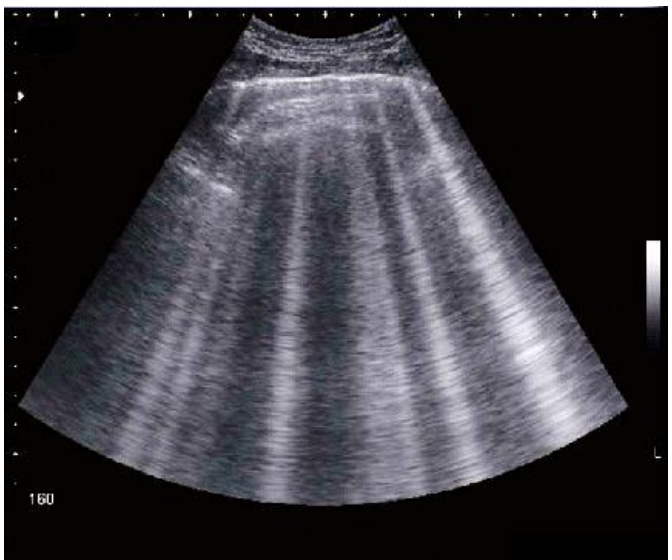

Considerando a imagem de ultrassom abaixo, analise as assertivas a seguir:

I. Esse padrão de imagem pode representar um paciente com doença intersticial pulmonar.

II. Esse padrão é conhecido como padrão A.

III. Esse padrão de imagem transposto para o modo M é visto como o “sinal do código de barras”.

IV. Esse padrão é comum em pacientes com insuficiência cardíaca perfil L.